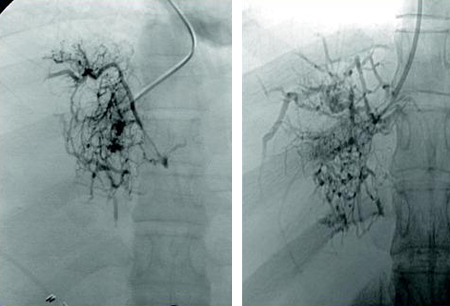

Hepatic venogram demonstrating 'spider web' and thrombus in the inferior vena cava

Liver Transplantation Journal. 2006;12:S21-S22; reprinted with permission of John Wiley & Sons, Inc.